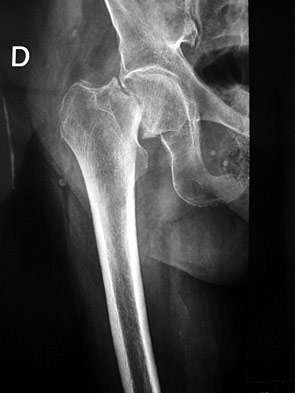

+ Atención de Fracturas y Lesiones Traumáticas:

Diagnóstico, reducción y tratamiento de fracturas, luxaciones y traumatismos óseos.

+ Corrección de Deformidades Óseas y Articulares:

Atención especializada en condiciones como pie plano, displasia de cadera y deformidades congénitas o adquiridas.

+ Consulta para Prótesis y Reemplazos Articulares:

Asesoramiento para candidatos a reemplazos de cadera, rodilla u otras articulaciones, así como seguimiento postoperatorio.